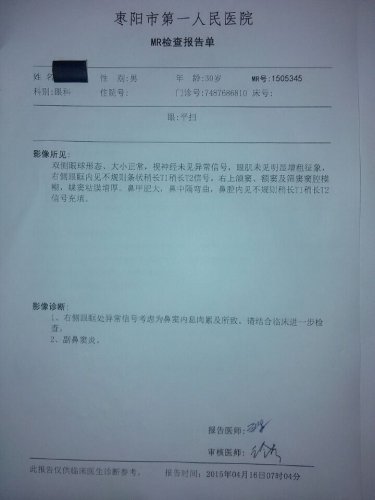

昨日(2015—04—15)MR影像报告:

03—27 影像图:

04—15 影像图